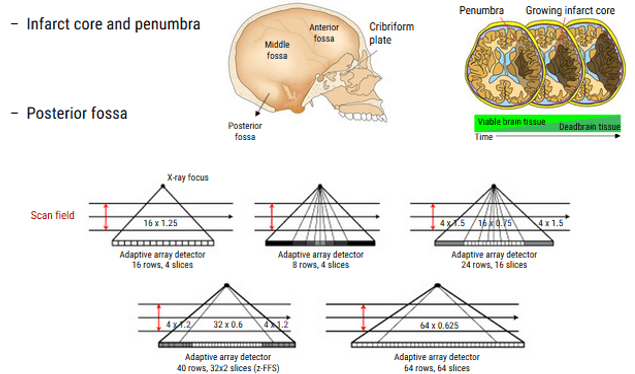

As we mentioned previously, the diagnosis, characterization, and localization in affected regions of the brain, are limited by the old techniques and the old CT scanner generations especially in these 3 regions: infarct core, penumbra and posterior fossa.

This anatomy coverage and resolution can be decreased by making 2 injections of contrast followed by 2 CT series. Unfortunately, this technique is limited for people who have poor renal function.

Another approach to decreasing coverage, is to move the scanner between two different brain levels, collecting data from each portion in seriatim. This toggle-table technique allows radiologists to capture a substantially greater portion of the brain on CT with a single bolus, although the temporal resolution of the resulting images may be impaired because the time between the sequential images of a single slice is extended. An associated risk of increased contrast and radiation dosage is also seen with these adaptive strategies.

However, the new technology of scanners made a development in perfusion CT. Some of which are the following:

- Higher number of detectors

- Wide Coverage of the region without moving the table and patient

- Radiation safety for the patient: lower exposure

- Better performance for the Perfusion CT Exam

The readily accessible and rapid technique that can help detect any acute ischemic stroke is the Perfusion CT Exa which will evaluate the parenchyma and determine the volume of infarct core and penumbra.